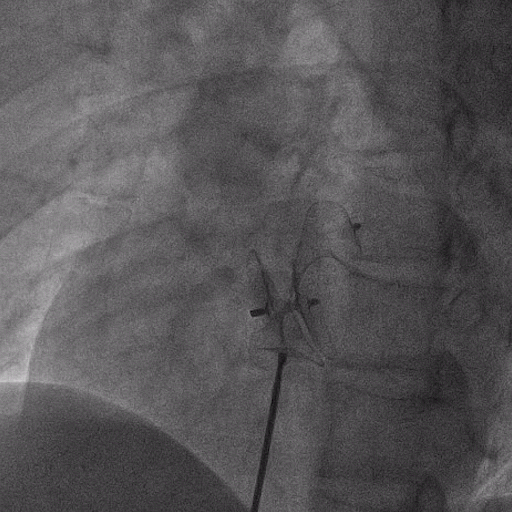

在獲得患者同意后,1月12日,尚福軍主任為患者進(jìn)行了PFO封堵術(shù)。術(shù)中造影可見封堵器殘余漏,尚福軍主任用精湛的技藝,順利通過封堵器殘余漏裂縫,將右心導(dǎo)管從右房送入左房,且順利到達(dá)肺靜脈;遂行卵圓孔未閉封堵術(shù)后殘余漏再次封堵;且完美釋放PFO封堵器,可見兩封堵器呈“馬蹄蓮”狀,再次術(shù)中造影未見殘余漏。